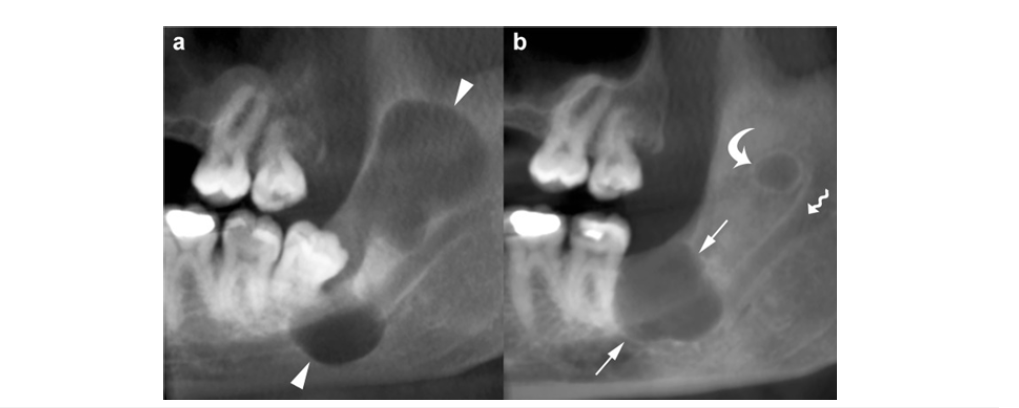

Despite these clues, OKCs can resemble other odontogenic lesions depending on their presentation. When associated with an impacted tooth, they may mimic a dentigerous cyst (Figure 9a). Multilocular OKCs located in the posterior mandible or ramus can resemble an ameloblastoma, while those in a periapical position or an edentulous area may simulate a radicular cyst. Consequently, dentigerous cysts, ameloblastomas, and radicular cysts remain the most frequent entities considered in the differential diagnosis of OKCs.

Figure 9:

Multiple OKCs may also occur in other syndromes, such as Noonan syndrome, Ehlers-Danlos syndrome and oral-facial-digital syndrome. In syndromic cases, OKCs typically appear at an earlier age (first or second decade), tend to arise more frequently in the posterior maxillary regions (Figure 9a), exhibit more aggressive behavior, and demonstrate a higher recurrence rate compared with non-syndromic OKCs [18]. A panoramic CBCT slice (1mm thickness) demonstrates two unilocular OKCs in the right and left maxilla (asterisks) in a young male diagnosed with Nevoid Basal Cell Carcinoma Syndrome (NBCCS). Both cystic lesions arise in the posterior maxillary segments and extend into the Maxillary Sinuses (MS). Although uncommon, multiple OKCs may occasionally be found in patients without any identifiable systemic condition. Nevertheless, when multiple OKCs are present, a syndromic association should be strongly considered until excluded. Individuals with multiple OKCs require ongoing clinical followup to monitor for the potential development of other systemic manifestations.